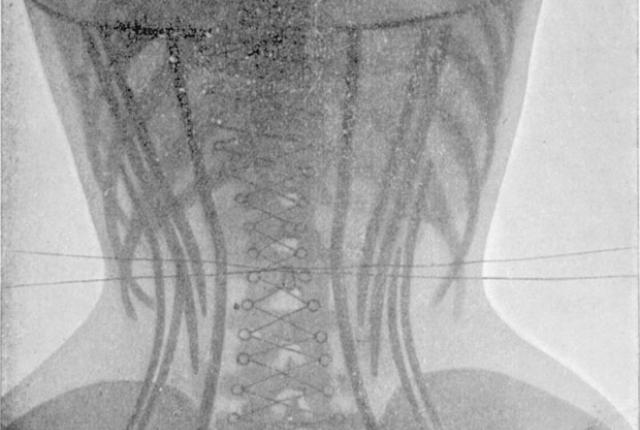

Корсеты

Знаете, что кажется мужчинам особенно скучным? Пышущий здоровьем женский организм, вот что! Зачем, вы думаете, в 19 веке сильный пол с таким усердием охотился на китов? Чтобы женщины могли утягивать свои тела корсетами из китового уса и калечить внутренние органы, конечно.